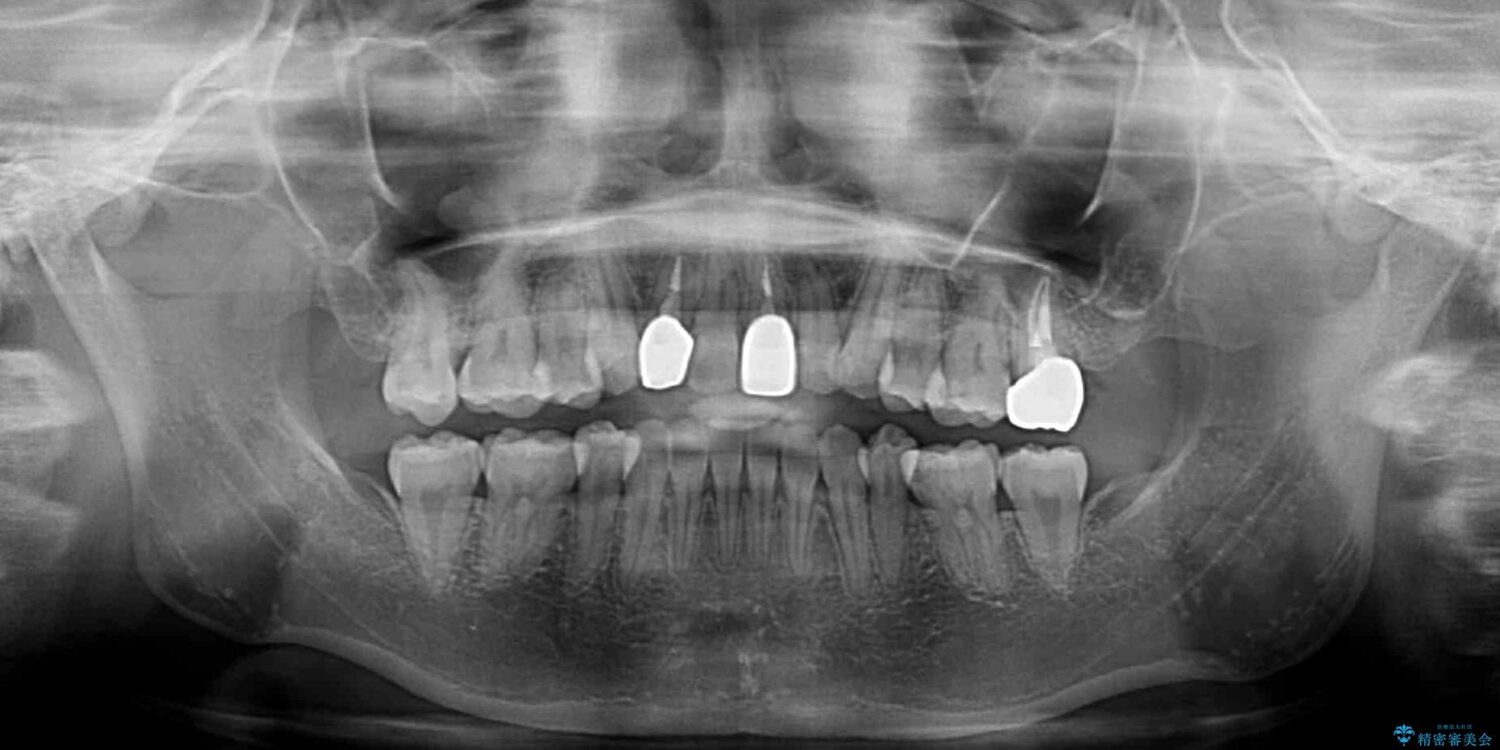

治療前

• 虫歯治療ついでに歯並びの後戻りを改善 インビザラインによる矯正治療 治療前画像